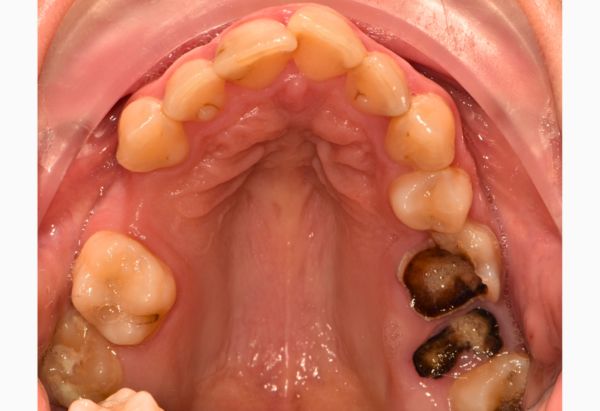

Before

Stabilisation Treatment